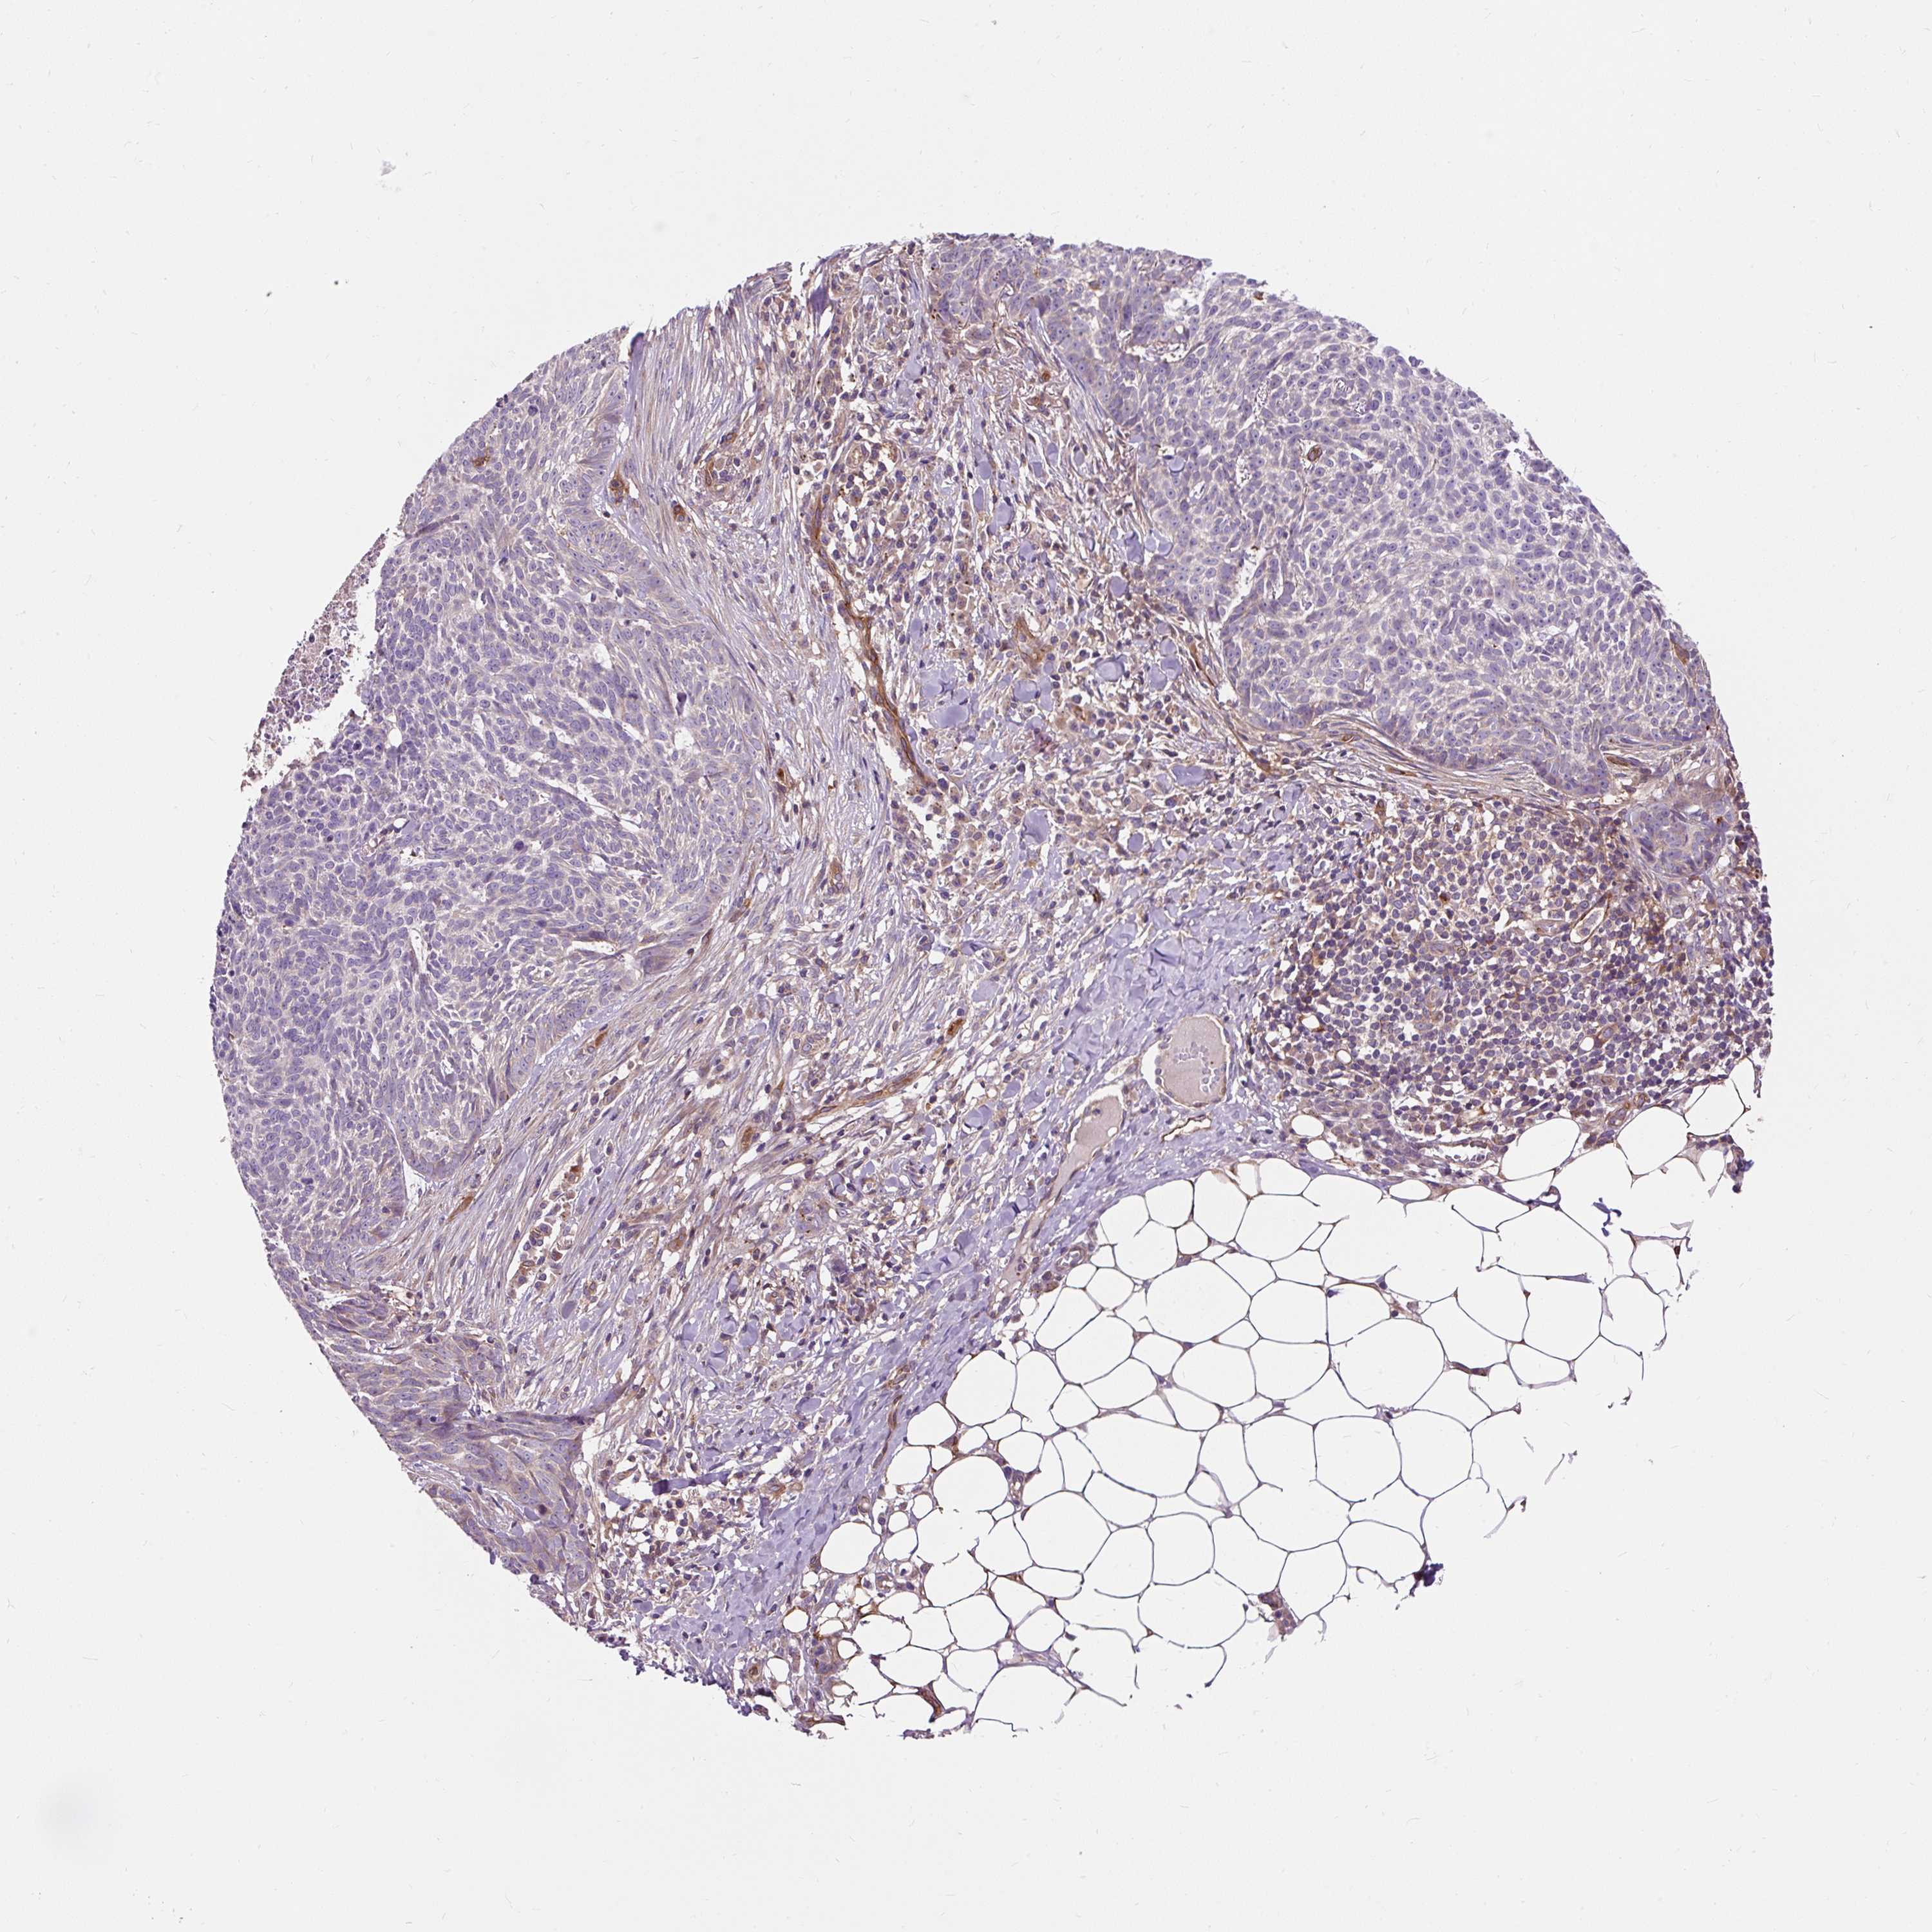

CANCER SKIN CANCER Show tissue menu

Basal cell and squamous cell cancer

SKIN CANCER - Protein expressioni

A mouse-over function shows sample information and annotation data. Click on an image to view it in a full screen mode. Samples can be filtered based on level of antibody staining by selecting one or several of the following categories: high, medium, low and not detected. The assay and annotation is described here.

Each image is clickable and will lead to virtual microscopy that enables deeper exploration of all samples and also displays staining intensity scores, fraction scores and subcellular localization as well as patient and tissue information for each sample.

Antibody HPA035823

Squamous cell carcinoma, metastatic, NOS

Basal cell carcinoma